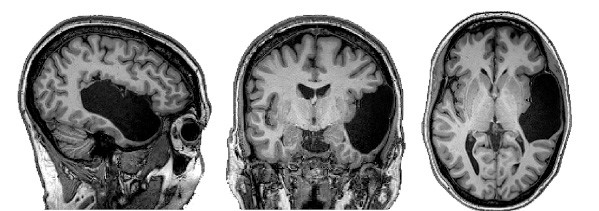

Рис. 7. Мозг пациентки EG. Черный участок на снимке – «дыра» на месте левой височной доли

Источник: Evelina Fedorenko et al / Neuropsychologia 2022

Однако теперь очевидно, что такие нарушения не только не всегда приводят к смерти человека, но могут вообще не влиять на его состояние. В конце концов девушку пригласили в Массачусетский технологический институт, где исследовали, как обрабатывает речь ее мозг и мозг здоровых людей.

Выяснилось следующее: у всех добровольцев с нормальным мозгом лингвистический центр находился там, где ему и положено быть – в левом полушарии, в лобной и височной долях. А у EG языковой центр располагался справа – в том полушарии, где сохранились обе нужные «языковые» доли. При этом уцелевшая левая лобная доля никак не реагировала на языковые стимулы.